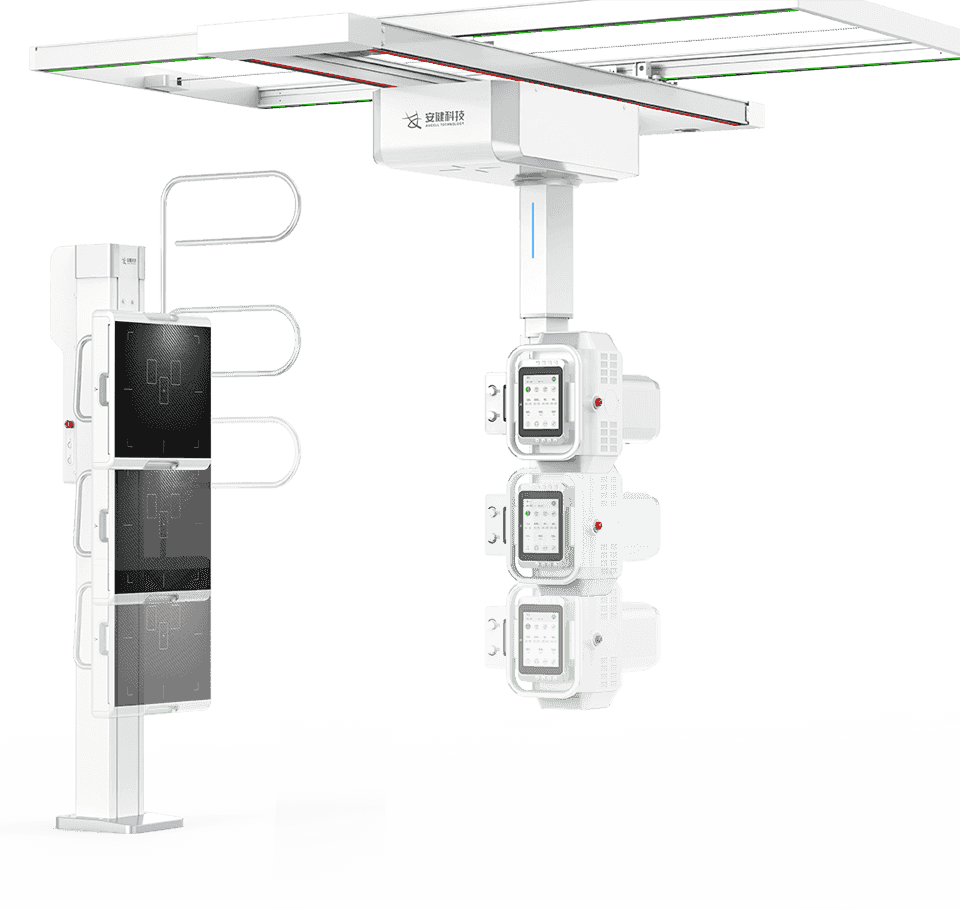

4D十轴联动运动系统

多功能悬吊式机械运动,全平衡稳定性设计,4D十轴联动技术,机架运动自如平稳,

配合电动升降床及多功能立式摄影架,轻松满足临床全体位摄影需求。

探测器、球管双向自动跟踪

探测器与球管可实现双向自动跟踪,

立卧位高精度实时同步,大幅提高临床检查效率。 -

全自动长骨拼接

一键式拼接摄影拍摄程序,快速进行分段摄影,后台

自动处理拼接影像,使拼接成像高效精准。 -

立卧位一键切换、—键到位

全自动智能运动控制,射频信号双向接收设计,

实现立卧位一键切换、一键到位,简化操作,提升效率。 -

电动升降床

超大行程运动范围,灵活应对儿童、老人、外伤患者上下床。

配备嵌入式感应解锁系统,轻松调节床高并有效避免患者误触。

动静双板自由切换

动态平板+静态平板双板配置,可实现毫秒级选板切换。

配合手自一体悬吊式机械运动系统,多体位拍摄转换轻松自如,大幅提升临床检查效率 -

低体位灵活拍摄

探测器和球管可降至紧贴地面,完成下肢多角度摄影,

减少病人移动,同时便于儿童立位、四肢拍片。 -